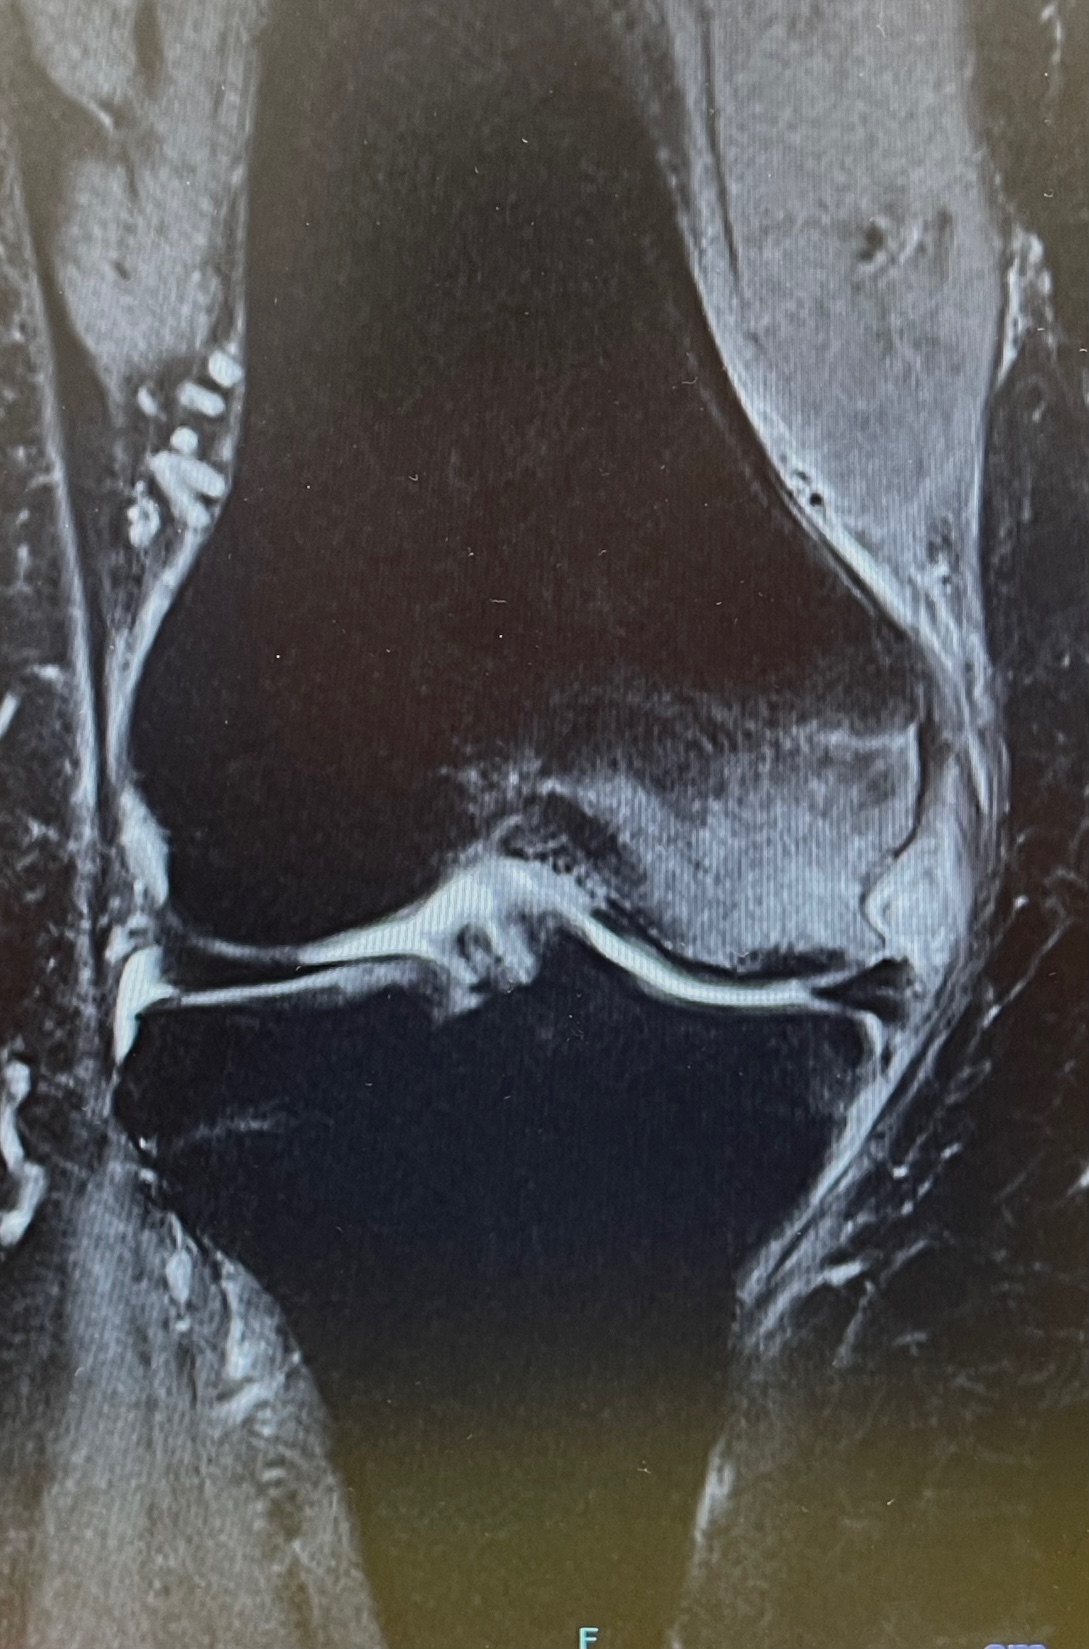

| Stage3 左X線像・右MRI像 |